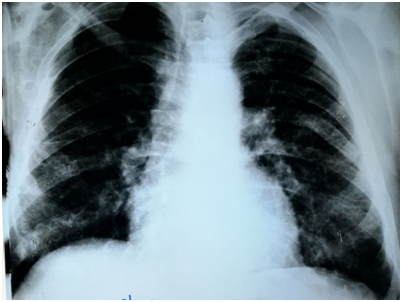

Chest Multi-Slice CTscan revealed several diffused interstitial reticular densities in both pulmonary fields with small nodular densities without enlargement of lymphatic nodes (Figure 3). Pelvis Multi-Slice CT scan revealed lytic lesions in hip and legs without invasion of adjacent tissues (Figure 4). We sent the Bronchial incisional biopsy taken by bronchoscopy and surgical incisional biopsy taken from left tibia to pathology department.

Figure 3 Chest MSCT showing several diffused interstitial reticular densities in both pulmonary fields with small nodular densities.

Pulmonary involvement is observed in 20-40% of LCH patients and can give symptoms, such as pneumothorax, dyspnea, tachypnea, and cough. Imaging studies of the lungs may reveal cysts and micronodular infiltrates.7 The patient had grade II dyspnea. CXR and MS- CT imaging of the lungs showed diffused interstitial reticular density. We performed Bronchoscopy and biopsy that showed histological features consistent with LCH.